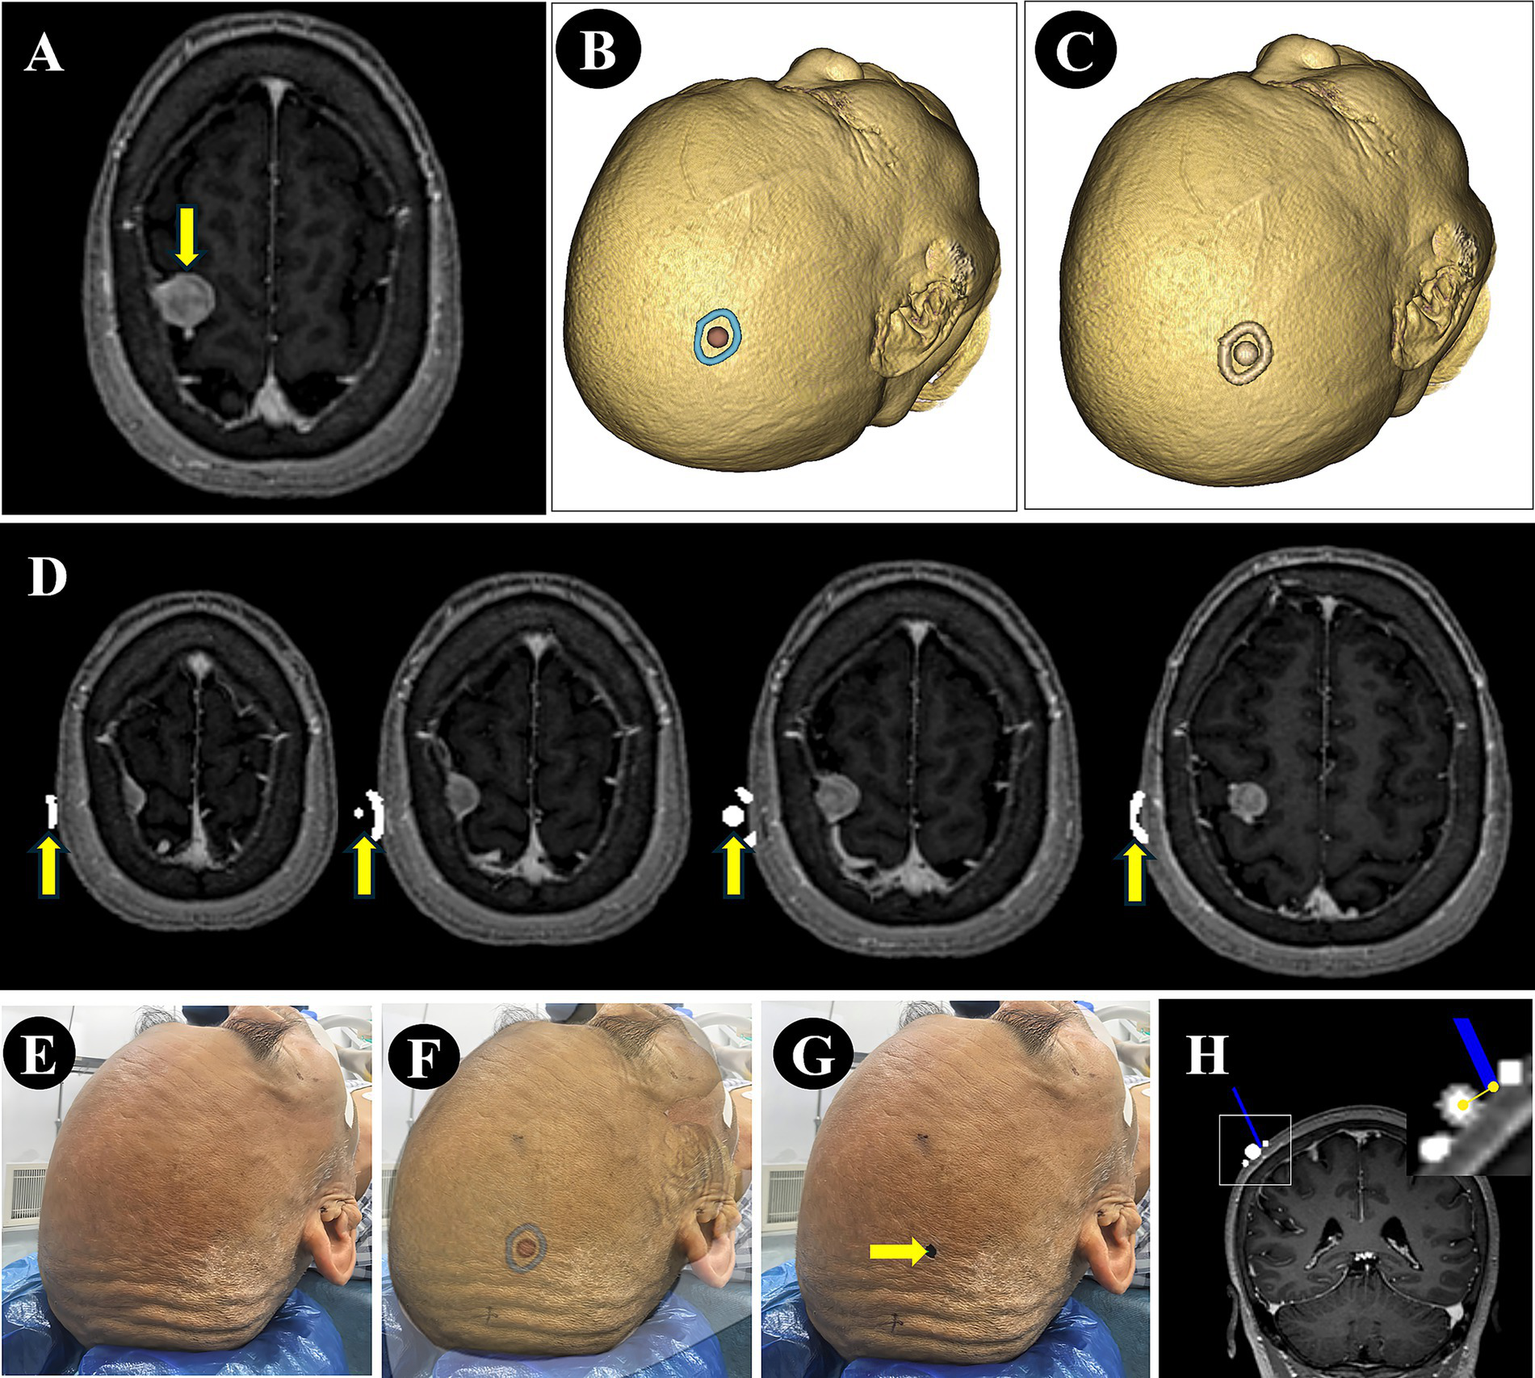

For patients in the NP-Guide group, after exporting the DICOM data, the 3D view was further adjusted to display the lesion contour and its center. This view was then captured using a mobile device running NP-Guide to enable projection-based localization during the surgery. The workflow for the data processing and measurement is shown in Figure 2.

Figure 2

Image processing and error measurement. (A) A right parietal lesion was shown on preoperative MRI (purple arrow). (B) The lesion boundary (blue) and center point (red) were reconstructed from preoperative imaging and the view was saved for NP-Guide localization. (C) The lesion boundary and center point were filled in grayscale and fused with the original image. (D) The fused image was resampled and exported in DICOM format, containing the lesion boundary and center point (yellow arrow). (E–G) The patient’s head was fixed (E), the NP-Guide projection was applied (F), and the lesion center was marked on the scalp (green arrow, G). (H) An optical navigation probe (blue) was placed on the marked point, and the ONS was used to measure the distance between the probe tip and the true lesion center.